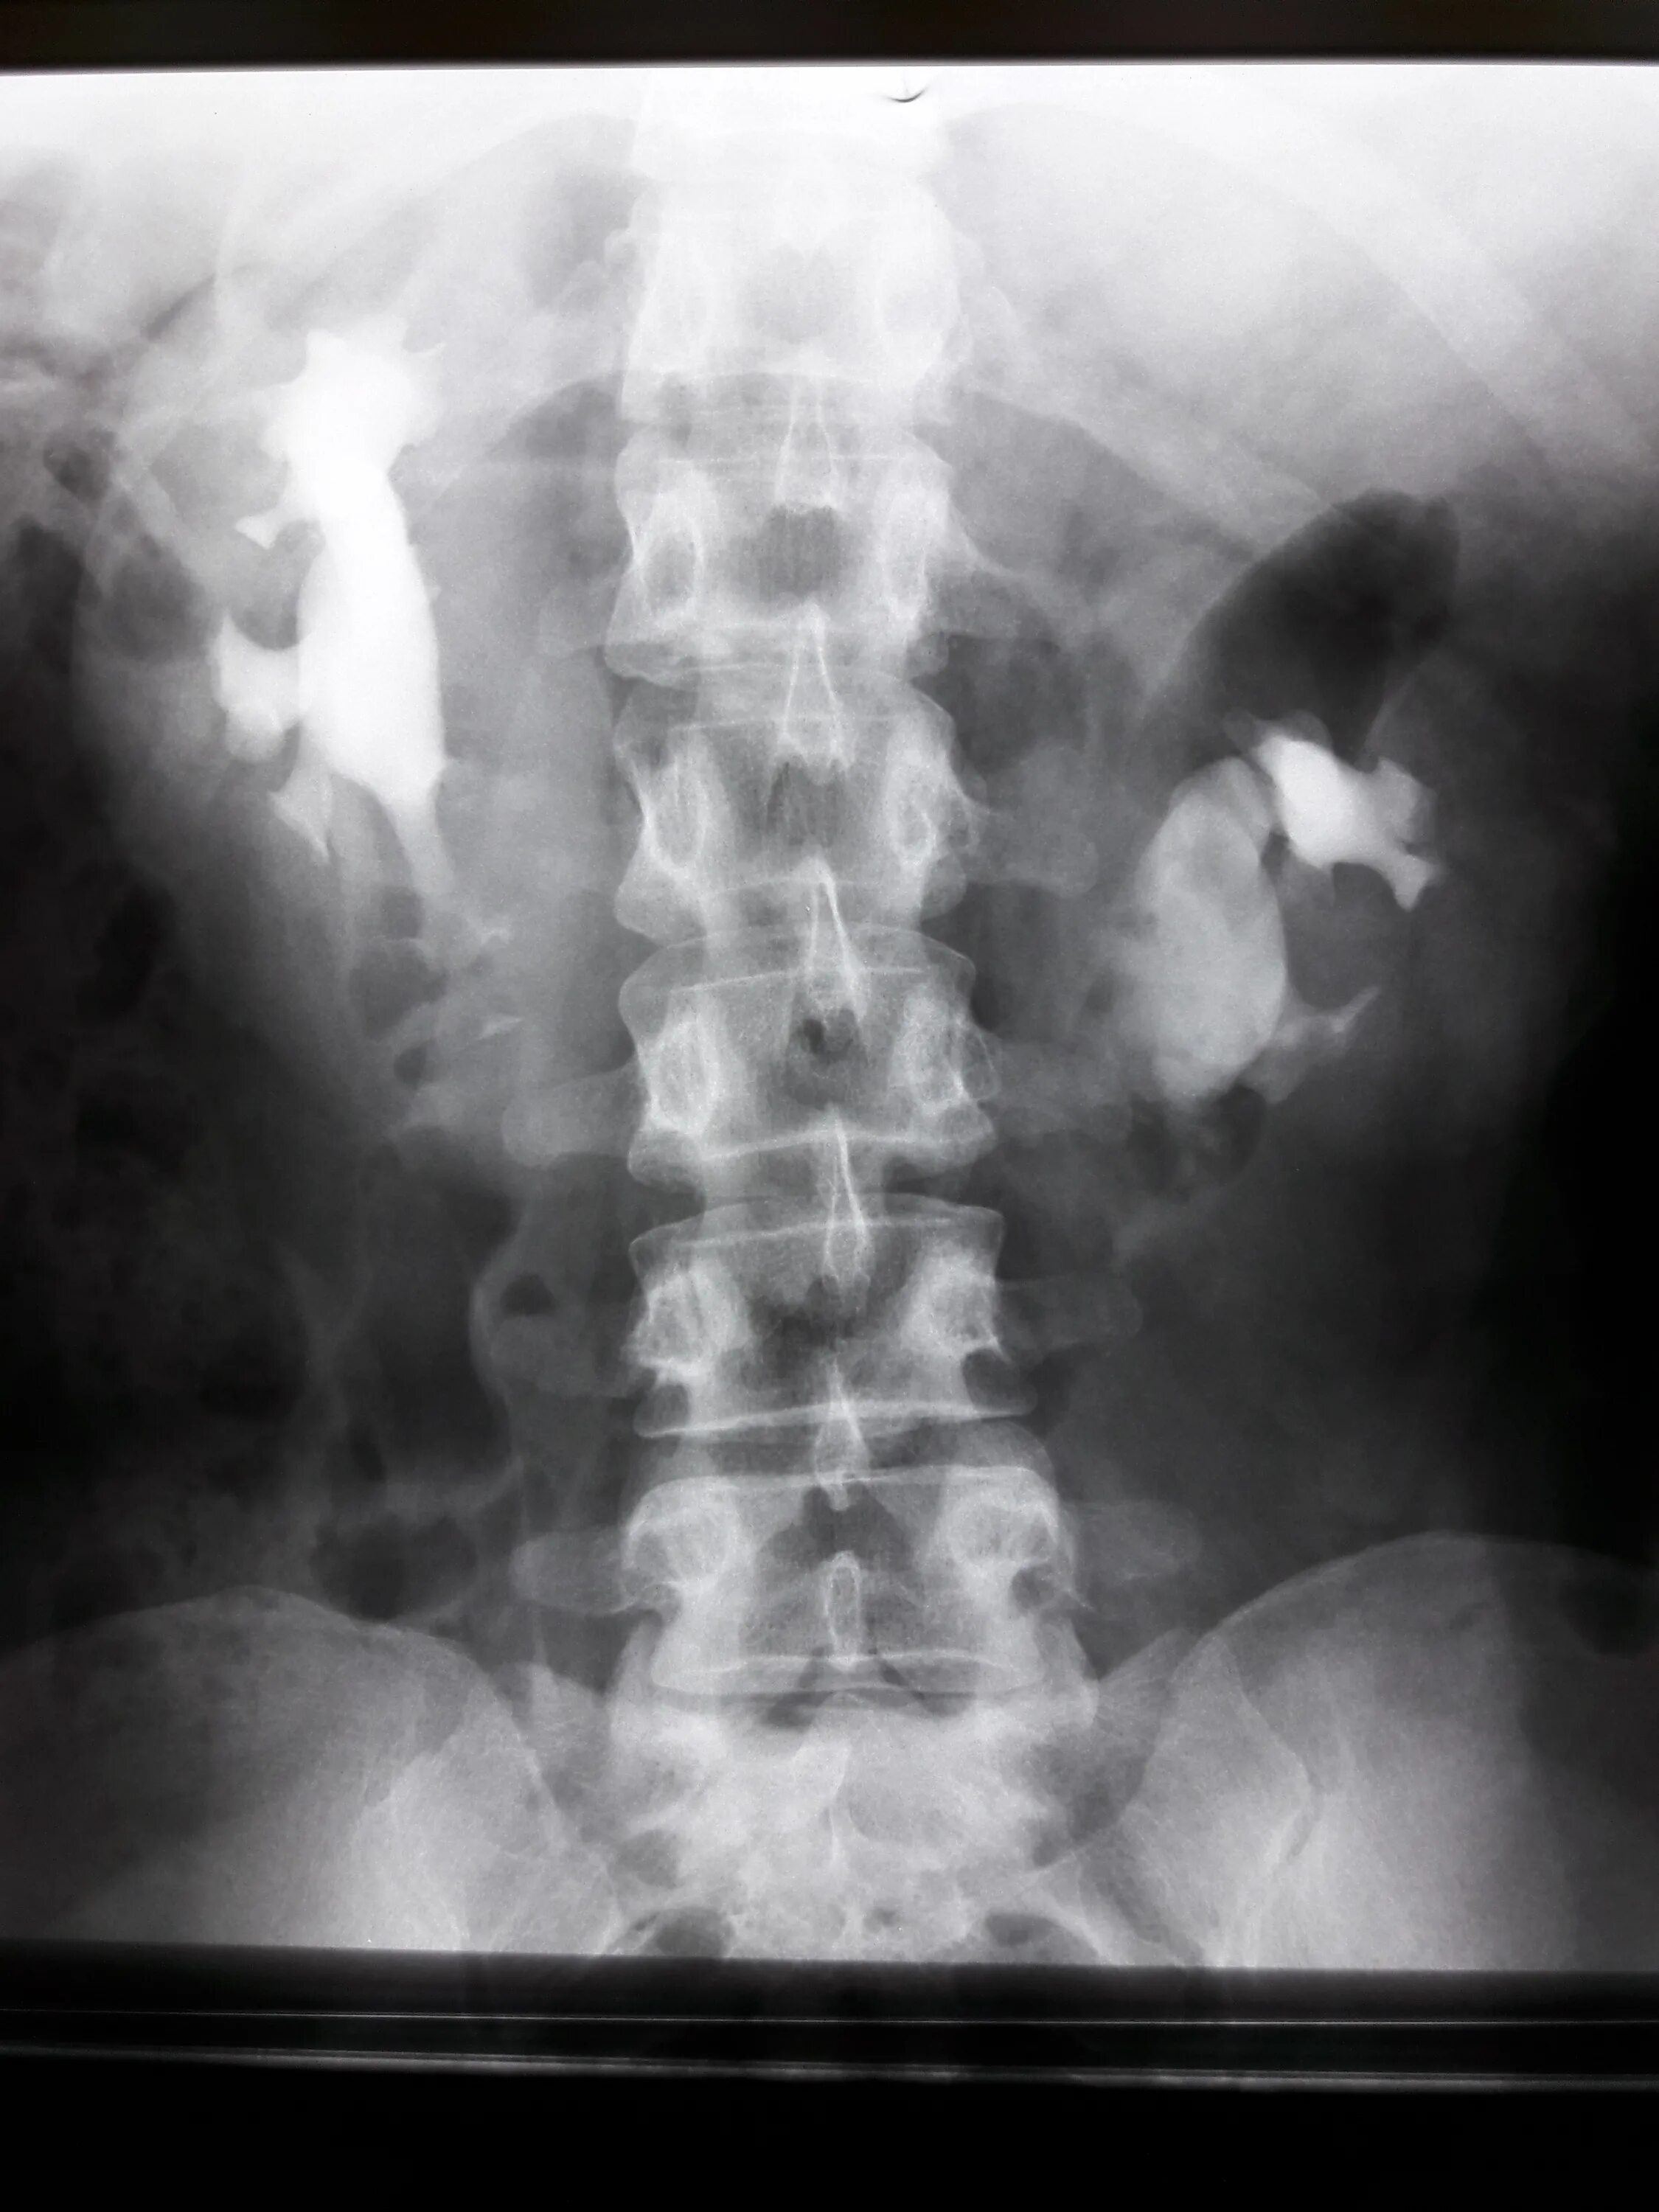

После урографии